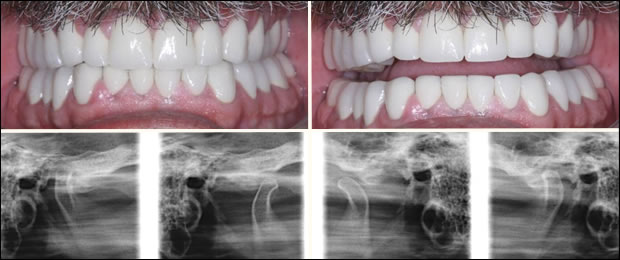

After

Post Op: Porcelain crowns and restored vertical dimension. Transcranial images of the temporomandibular joints, closed and open, right and left, respectively.